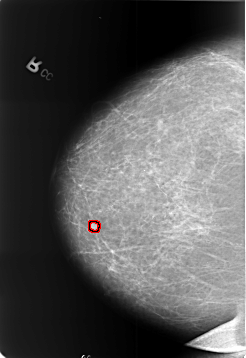

FILE: B_3391_1.RIGHT_MLO.OVERLAY

TOTAL_ABNORMALITIES 1

ABNORMALITY 1

LESION_TYPE MASS SHAPE ROUND MARGINS CIRCUMSCRIBED

ASSESSMENT 2

SUBTLETY 3

PATHOLOGY BENIGN

TOTAL_OUTLINES 1

BOUNDARY